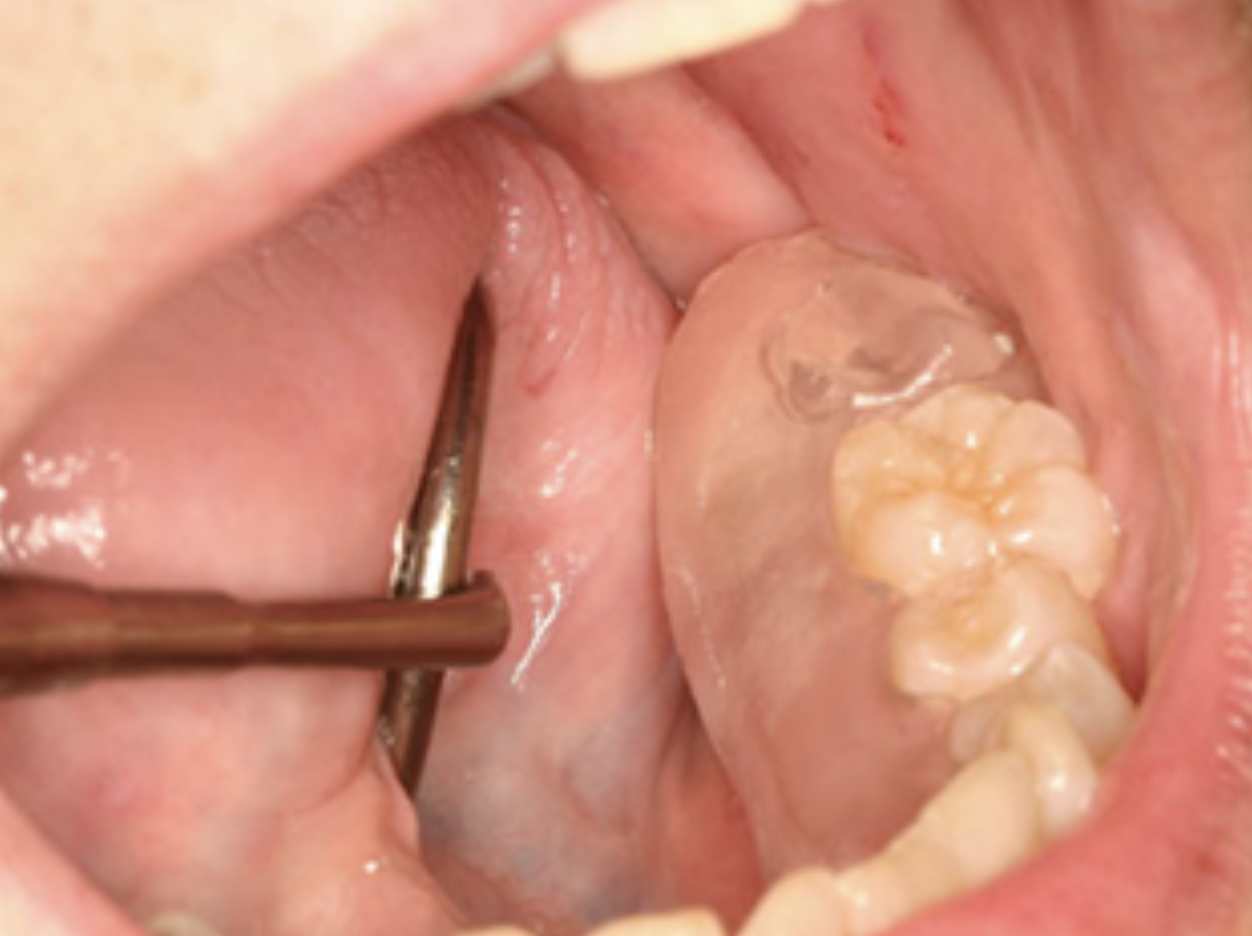

Việc điều trị nhằm mục đích làm giảm các triệu chứng hơn là chữa lành vết thương hoàn toàn. Các cạnh xương sắc nhọn có thể được làm nhẵn bằng dũa xương (bone file) mà không cần gây tê tại chỗ vì xương không còn sống. Các mảnh xương di động, hoặc mảnh xương "mục", cũng có thể được loại bỏ bằng cây nạo hoặc kẹp cắt (Hình 5).

Cơn đau trong hầu hết các trường hợp là do nhiễm trùng mô mềm lân cận thứ phát, có thể được điều trị bằng thuốc kháng sinh tại chỗ và/hoặc toàn thân. Trong trường hợp viêm mô mềm mạn tính hoặc có mủ lớn, bệnh nhân có thể cần dùng kháng sinh dài ngày. Chỉ định phẫu thuật xâm lấn nên tránh ở phần lớn bệnh nhân. Nếu cơn đau vẫn tiếp tục xảy ra khi ăn, mặc dù đã điều trị bảo tồn và kiểm soát nhiễm trùng, thì việc chế tạo stent phẫu thuật có thể có hiệu quả trong việc giảm hoặc loại bỏ các triệu chứng (Hình 6).